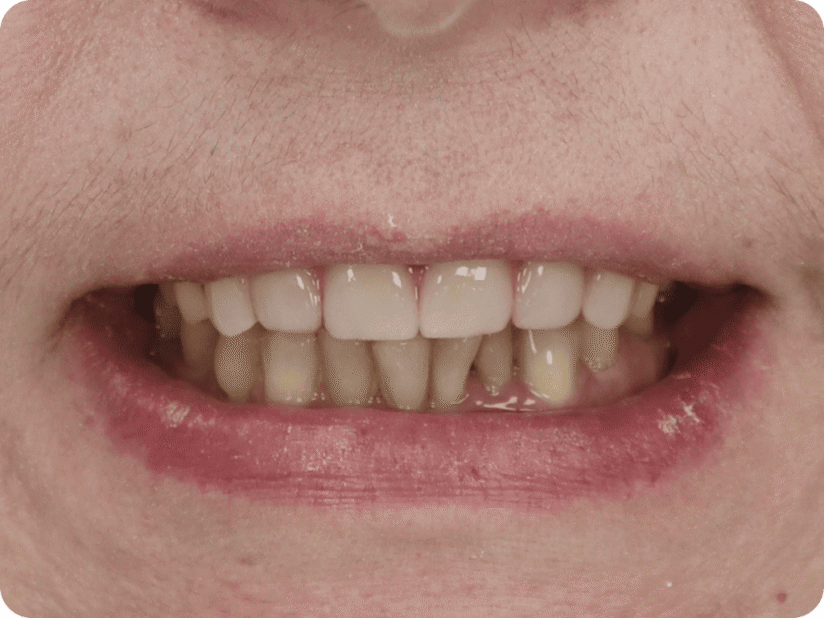

Ситуация до лечения

Пациент обратился с жалобами на эстетические недостатки.

Поставлен диагноз: частичная адентия.

Моляры на верхней челюсти отсутствуют